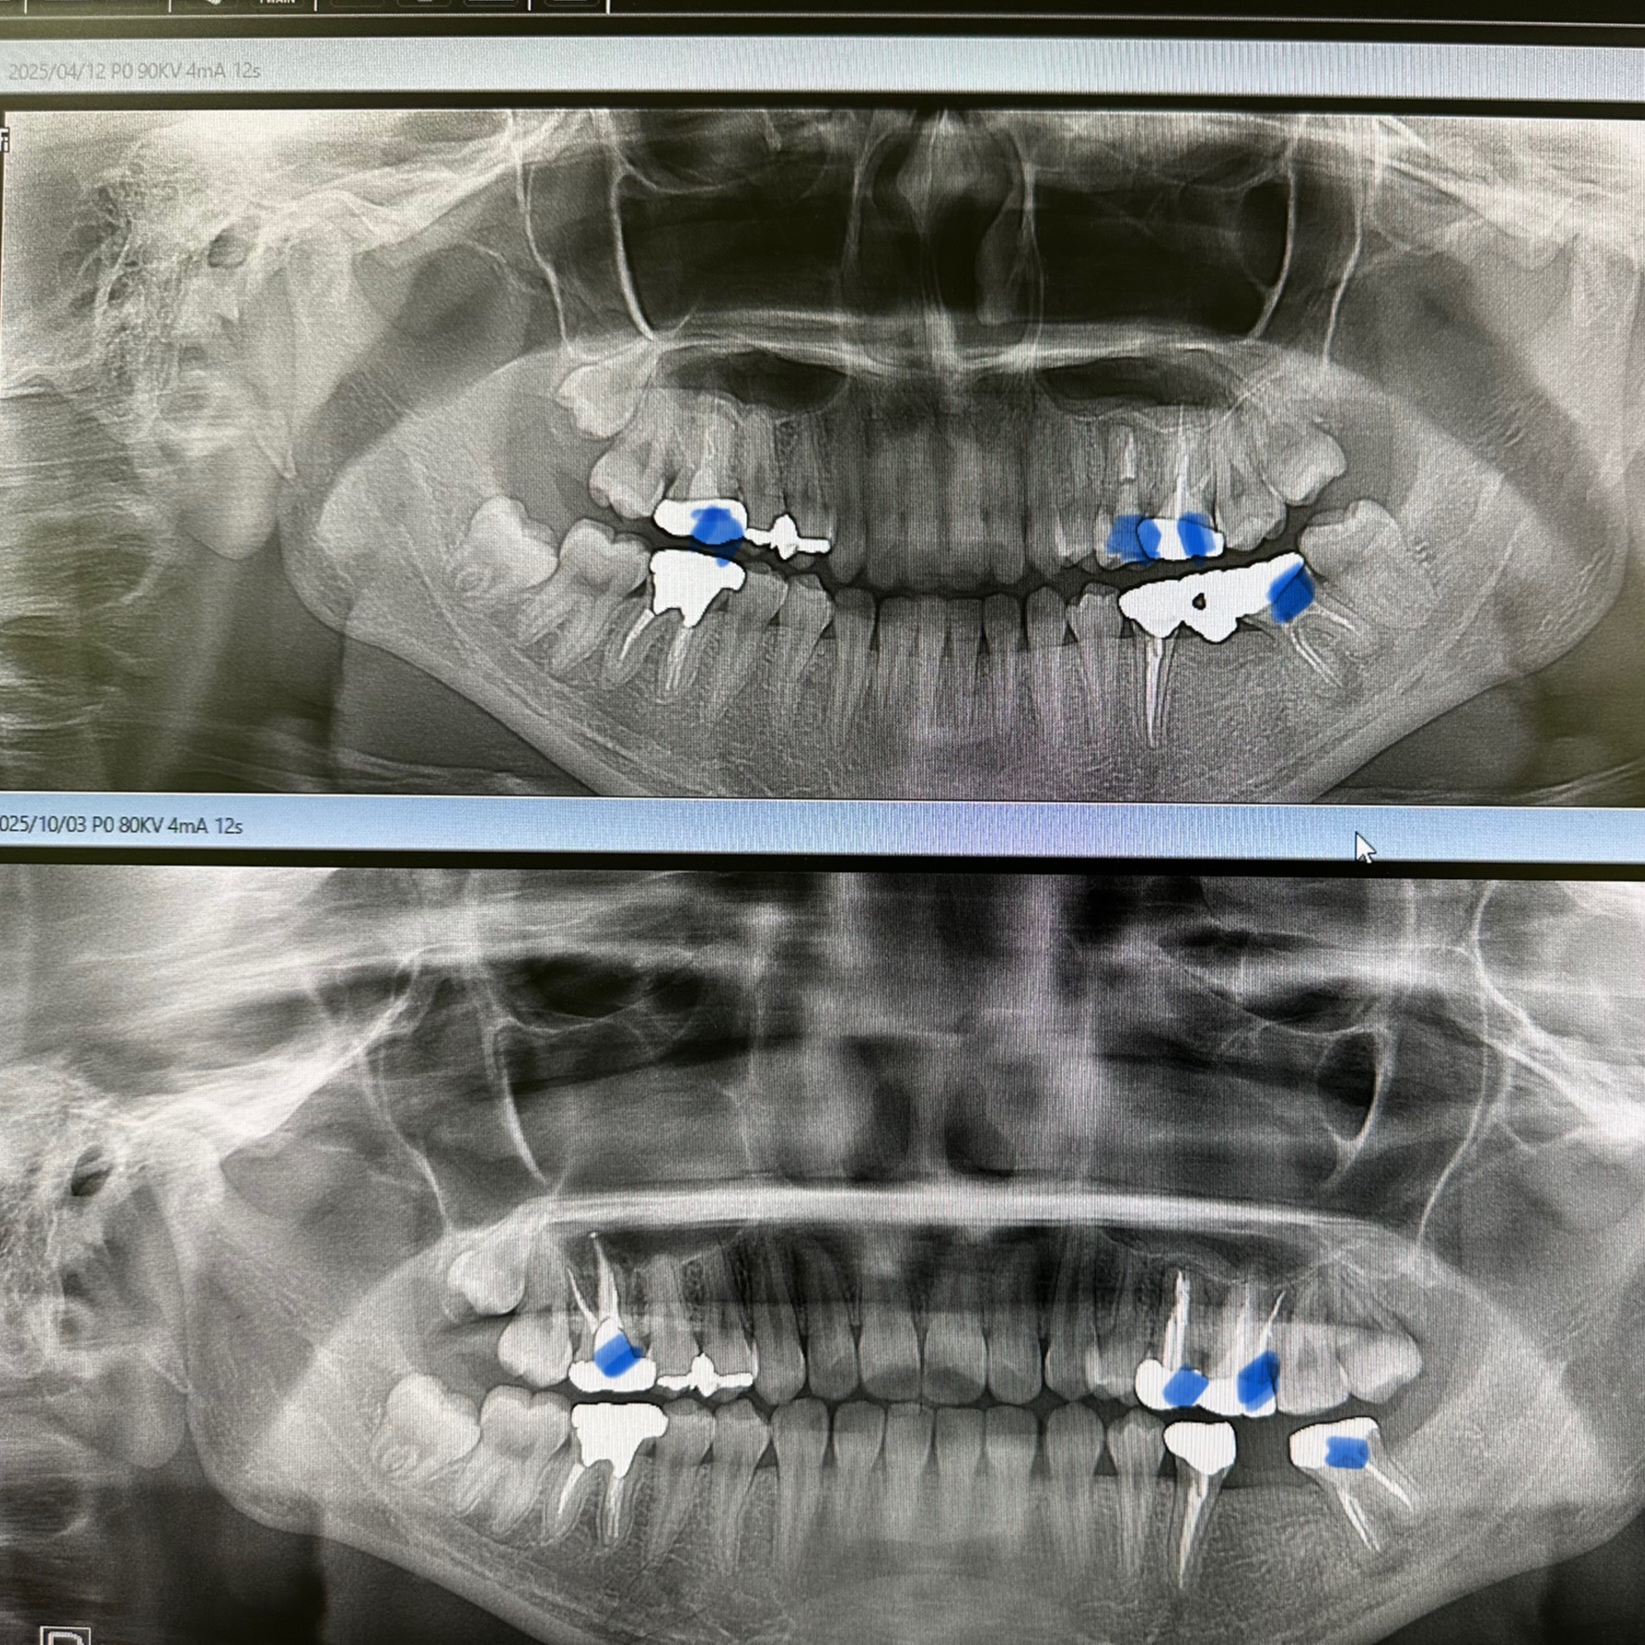

ネチネチ、チマチマ系の根管治療4本

パラタルプレートの再生、ヤグレーザー併用の根管治療のみ

経過みないとね、自然治癒力は素晴らしい!

外科処置の勇み足にならない為の良い症例

最小侵襲で治癒導くが重要

CT撮影は、算定要件満たしてない為に無料😭

咀嚼に耐え得る歯は保存!